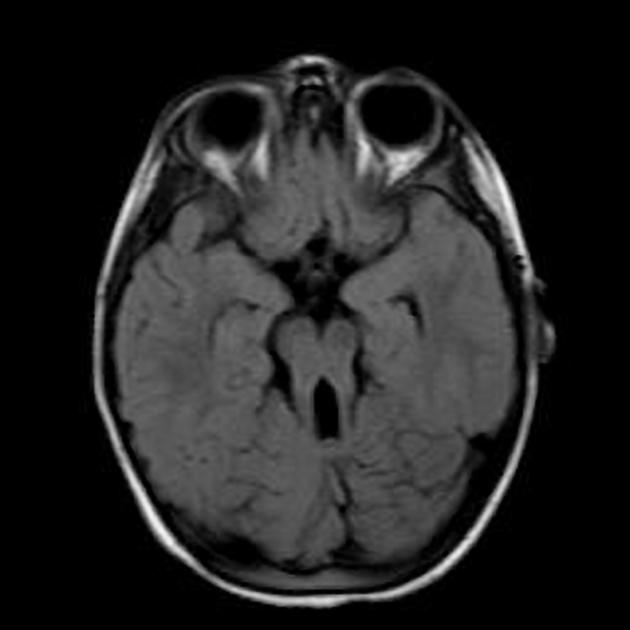

ODS

central pons

hypodense on CT

can be diffusion restricting

hyperintense on T2/FLAIR